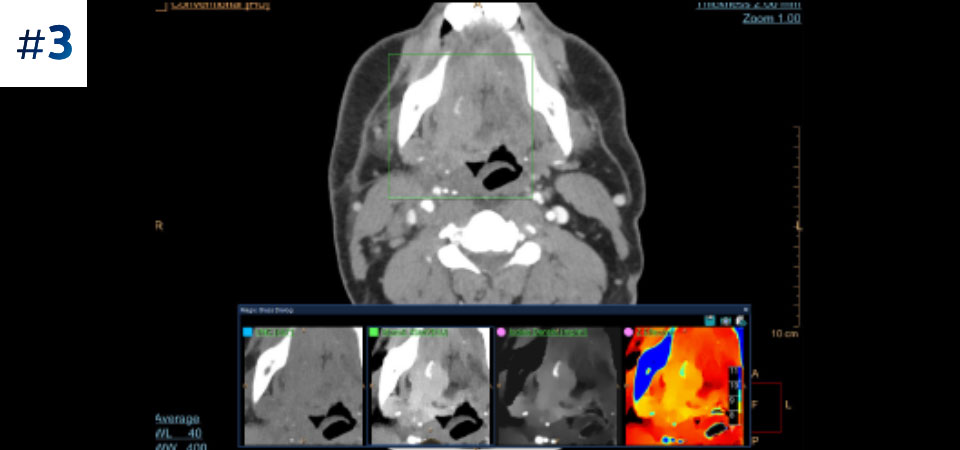

Can you solve the mystery diagnosis using spectral?

Go beyond conventional CT. See how layers of spectral-detector results can enhance your diagnostic confidence.

- Toggle view

Neck mass

Ready to see if you're right?

Check your answers here